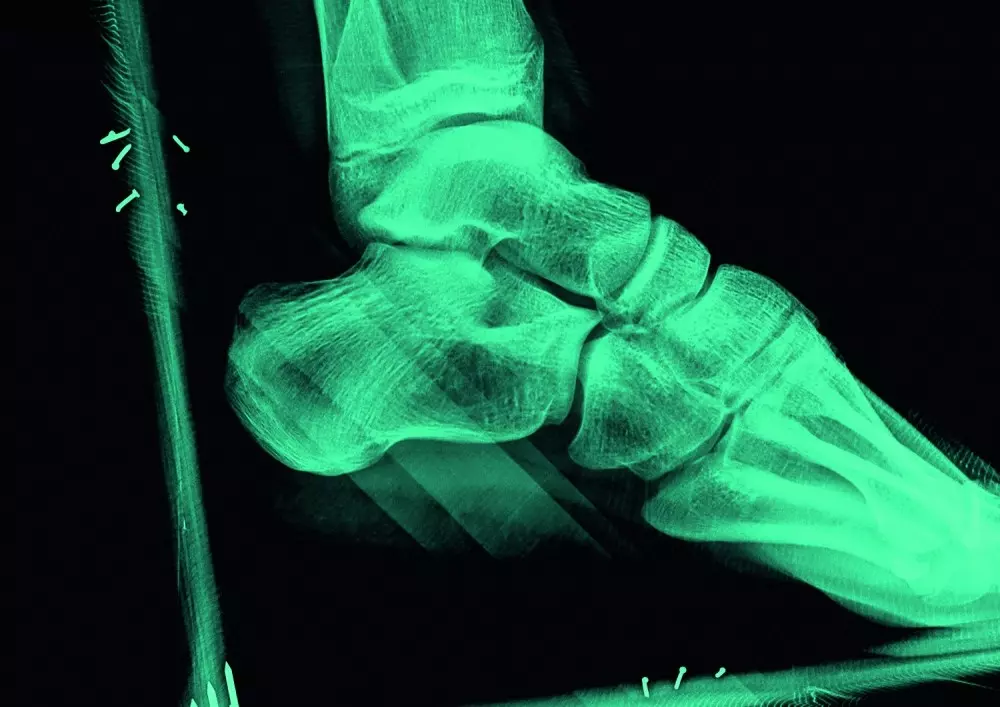

Skręcenia stawu skokowego występują bardzo często – dotykają zarówno sportowców, jak i osoby, które nie prowadzą aktywnego trybu życia. Jednak mimo powszechności tego urazu, należy pamiętać o tym, że może on wiązać się z powikłaniami. Ponadto istnieje ryzyko uszkodzenia innych struktur leżących w obrębie tego stawu. Nawiązując do tych częstych problemów, autor opisuje anatomię stawu, przyczyny skręcenia stawu skokowego wraz z analizą biomechaniczną, diagnostykę, odpowiednie testy funkcjonalne oraz leczenie.

W dziale „Z praktyki gabinetu” będą mogli zapoznać się Państwo z tekstem pt. „Stopa wydrążona – obraz kliniczny oraz postępowanie diagnostyczne”. „Stopa wydrążona to wspólne określenie schorzenia występującego w kilku różnych postaciach klinicznych. Cechą dla wszystkich form tej wady jest nadmiernie uniesiony łuk w płaszczyźnie strzałkowej, który nie ulega spłaszczeniu na skutek obciążenia masą ciała” – pisze ekspertka. To ważna, jednak wciąż nie do końca poznana wada postawy. W najnowszym numerze przybliżymy Państwu to zagadnienie na przykładzie przypadku 14-letniej pacjentki.